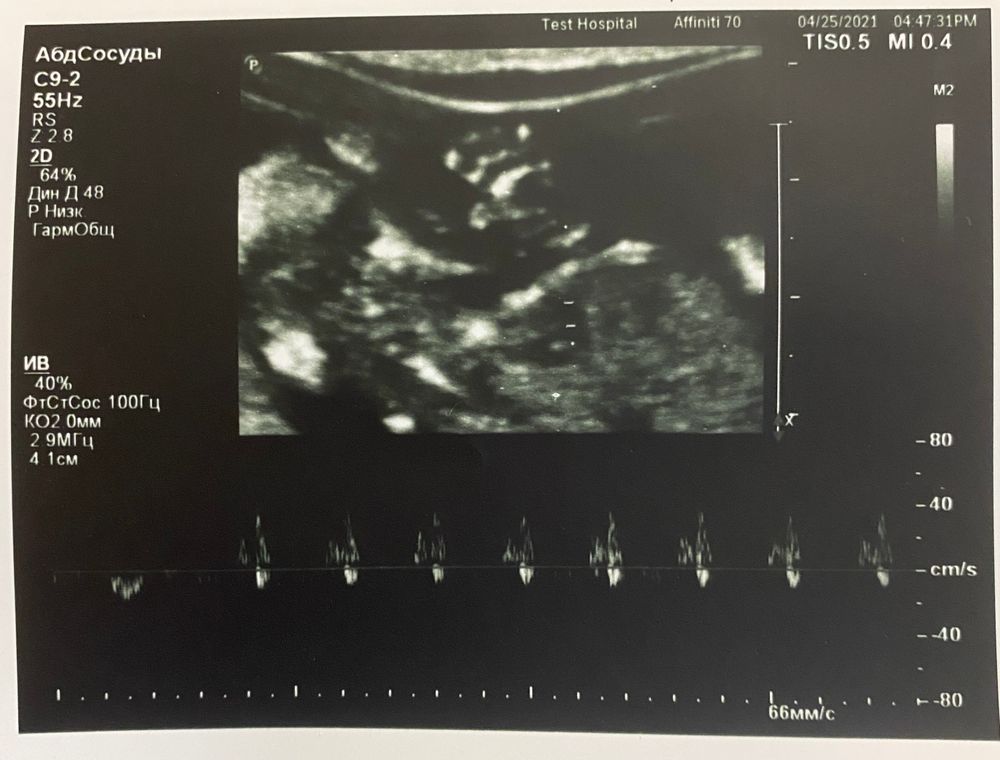

А дальше узист сказала, что это на 100% мальчик 🙈😁 что между ножек явно формируется писюн (на фотке ниже в самом центре) вот что то я сомневаюсь, неужели на таком сроке можно так точно определить? (Не по углу наклона, а просто по внешнему виду?) Как думаете?